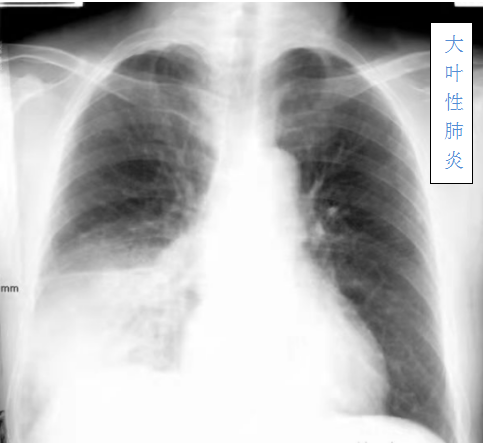

大叶性肺炎主要是由肺炎链球菌引起,病变累及一个肺段以上肺组织,以肺泡内弥漫性纤维素渗出为主的急性炎症。临床上起病急骤,常以高热、恶寒开始,继而出现咳嗽、胸痛、咳铁锈色痰、呼吸困难等,并有肺实变体征及外周血白细胞计数增高等。

儿童大叶性肺炎具有以下特征:一、起病急,发展快,病情重,表现不典型,病初以高热起病,少有肺部症状及肺部体征,一周后开始出现大叶性肺炎,易合并胸膜炎等。二、高热可持续一周或时间更长,咳嗽剧烈,一般总病程16~43天,住院时间为8~28天。三、听诊可闻及湿罗音,或呼吸音减弱、不对称,部分患者伴有胸疼。四、周围血白细胞不高,中性偏高,病原学检查未发现较为统一的病原体。影像学检查可见:均为大片状或斑片状密度增高影,局限于一个或多个肺段或肺叶。近三分之一的患者合并有胸膜炎或胸膜黏连或胸腔积液等。五、有群体发病的趋势,幼儿园里往往有多人发病,且症状相似,甚至幼儿园里有一半人发病,也有一家人相继发病的情况,说明本病有一定的传染性。